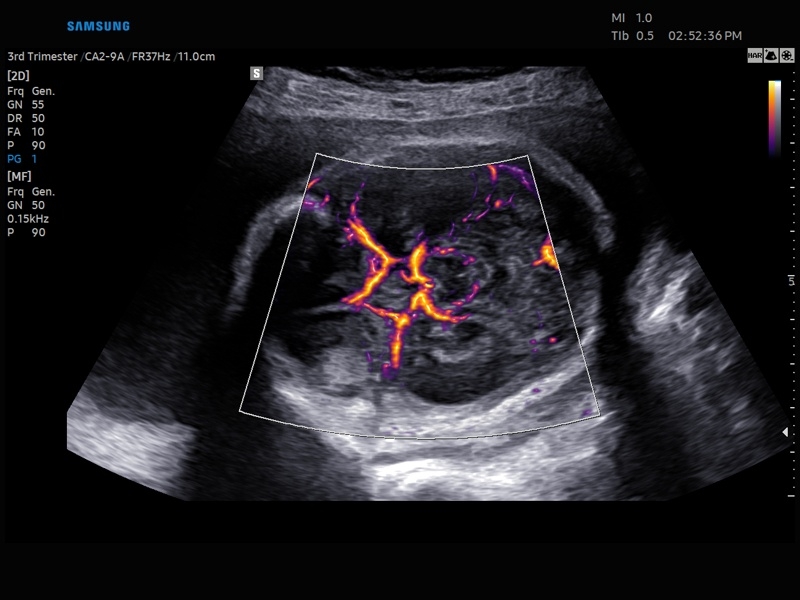

• Акушерство и гинекология

• Модуль MV-Flow – программа (режим), позволяющая визуализировать кровоток в микроциркуляторном русле с высоким разрешением без использования контраста.

• Модуль LumiFlow – программа отображения кровотока с объемной графикой для лучшего понимания архитектоники сосудистого русла.

• Программа SEE Stream – режим недопплеровской визуализации кровотока в реальном масштабе времени.

• Модуль MV-Flow - программа (режим), позволяющая визуализировать кровоток в микроциркуляторном русле с высоким разрешением без использования контраста.